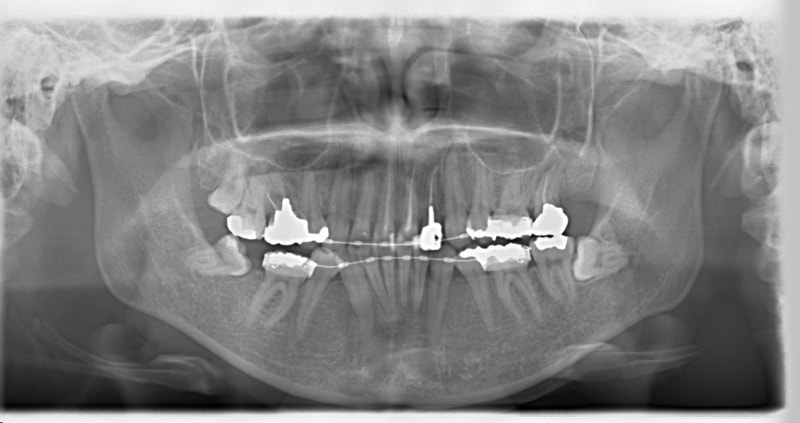

右下7番欠如歯(保存不可能歯につき抜歯)右下8番利用

治療前